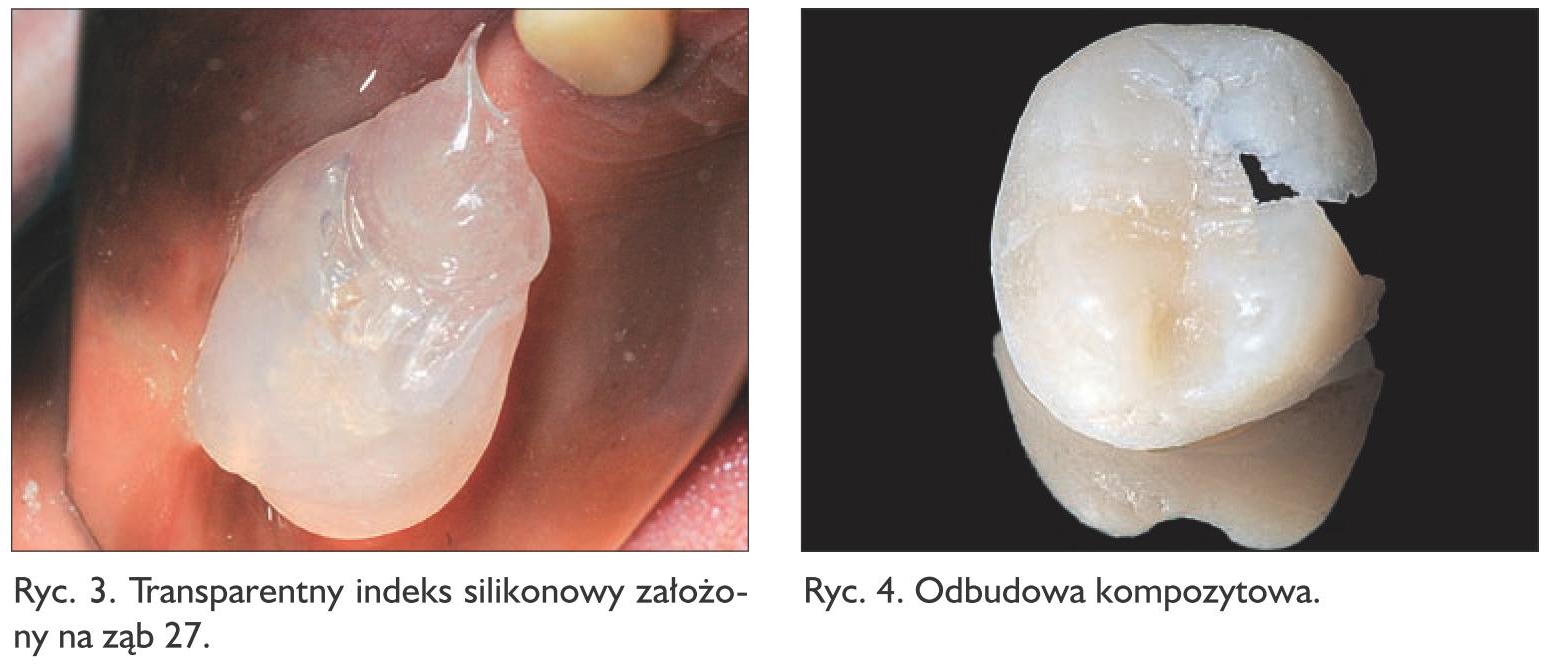

Usunięto nieszczelne wypełnienie klasy I, ubytek oczyszczono z tkanki próchnicowej (ryc. 1). Na podstawie wax-upu (ryc. 2) wykonano transparentny indeks silikonowy (Elite Glass, Zhermack), który przymierzono na opracowany ząb 27 (ryc. 3). Indeks zdjęto z zęba, ubytek i ściany zewnętrzne posmarowano cienką warstwą żelu glicerynowego. Do indeksu nałożono materiał kompozytowy Estelite Posterior PA3 (Tokuyama Dental), dokładnie skondensowany, w jednej warstwie. Indeks z nałożonym niespolimeryzowanym materiałem wprowadzono ponownie na ząb, dociskając tak, by uzyskać sprawdzone wcześniej stabilne położenie, a tym samym doprowadzić do wypłynięcia nadmiarów kompozytu. Zastosowany materiał kompozytowy umożliwia wygodną i spokojną pracę, bez ryzyka wcześniejszej polimeryzacji, a jego właściwości fizyczne dają pewność co do odpowiedniej wytrzymałości mechanicznej wykonanego uzupełnienia. Po usunięciu nadmiarów materiał spolimeryzowano światłem lampy polimeryzacyjnej, poprzez transparentny indeks silikonowy, 60 sekund z każdej strony. Zdjęto indeks, a każdą powierzchnię znajdującej się na zębie odbudowy dodatkowo doświetlono. Następnie odbudowa została ostrożnie podważona zgłębnikiem w celu jej usunięcia z ubytku. Uwolnioną pracę (ryc. 4) dodatkowo doświetlono od strony wewnętrznej. Wykonaną odbudowę odtłuszczono, przemywając ją alkoholem izopropylowym. Gdy stosuje się metodę półpośrednią, nie stanowią problemu wycienienia odbudowy, w tym wypadku widoczne na powierzchni zgryzowej i przedsionkowo. Były one odwzorowaniem cienkiej warstwy wosku nałożonego na modelu, co wynikało z sytuacji klinicznej. Gdyby jednak – w innym przypadku – istniała potrzeba nadbudowy takich miejsc (np. gdyby niedomiar powstał na skutek uszkodzenia pracy przy jej uwalnianiu z zęba), na kolejnym etapie mogłyby one zostać uzupełnione tym samym materiałem kompozytowym, z którego praca została wykonana.